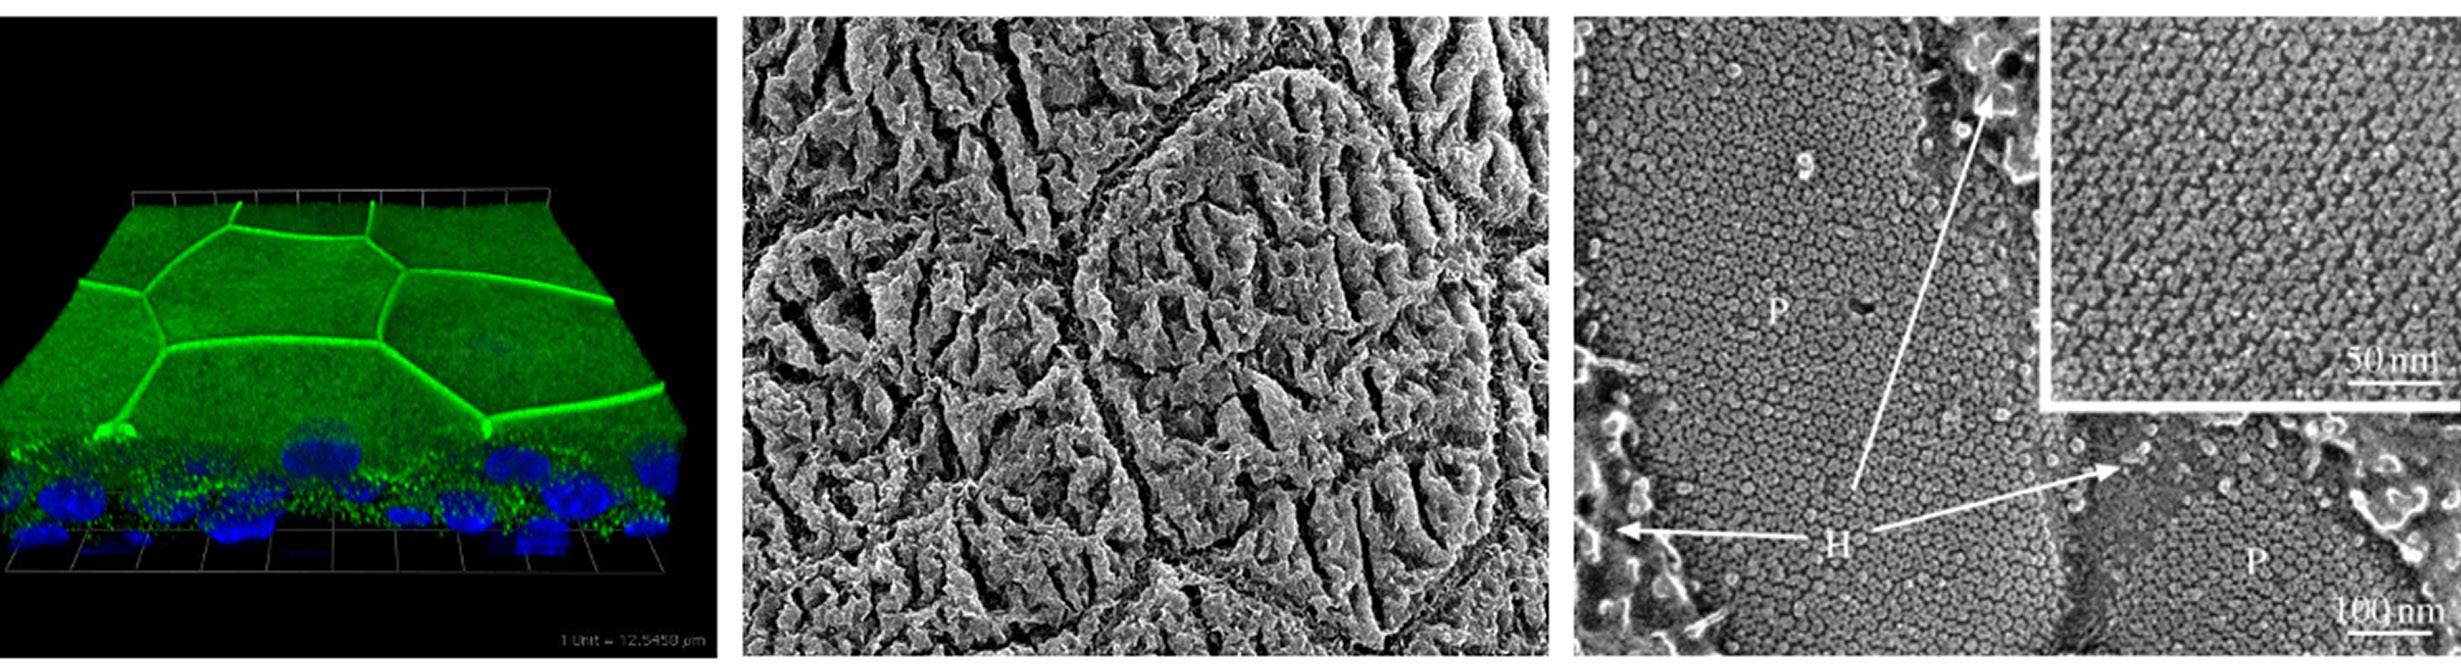

Figure 1. Electron microscopic image of a uropathogenic E.coli bacterium. Notice the hairlike filaments, called fimbriae, radiation from the bacterial surface, which mediate bacterial attachment. At the tip of each fimbrial filament is a protein called FimH which mediates attachment to the surface of bladder cells.

Figure 2. Microscopic images of cells lining the mouse bladder. Shown on the left is a stained cross-section of the bladder highlighting the tight junctions between adjacent cells (green) which serve as a barrier against urine. Shown in the middle is a scanning microscopic image of octagonal shaped bladder cells. On the right is a high-resolution image showing the cell surface uroplakin structures on the uroepithelium which resemble chain mail.

Figure 3. Scanning electron microcopy of the lining of the infected bladder. Shown above are numerous bacteria bound to the surface of the bladder. Below is a higher magnification of the same image revealing several bacteria in the process of entry into the epithelial lining of the bladder.

Figure 4. Micrograph showing uroepithelial cells shed from a patient with a UTI. Notice the large number of adherent bacteria found on the bladder cells. Shedding of epithelial cells is a powerful mechanism to reduce bacterial load in the bladder.

Figure 5. Cross-section of the mouse bladder weeks after a UTI. Notice the clumps of intracellular quiescent bacteria harboring in bladder cells (red).